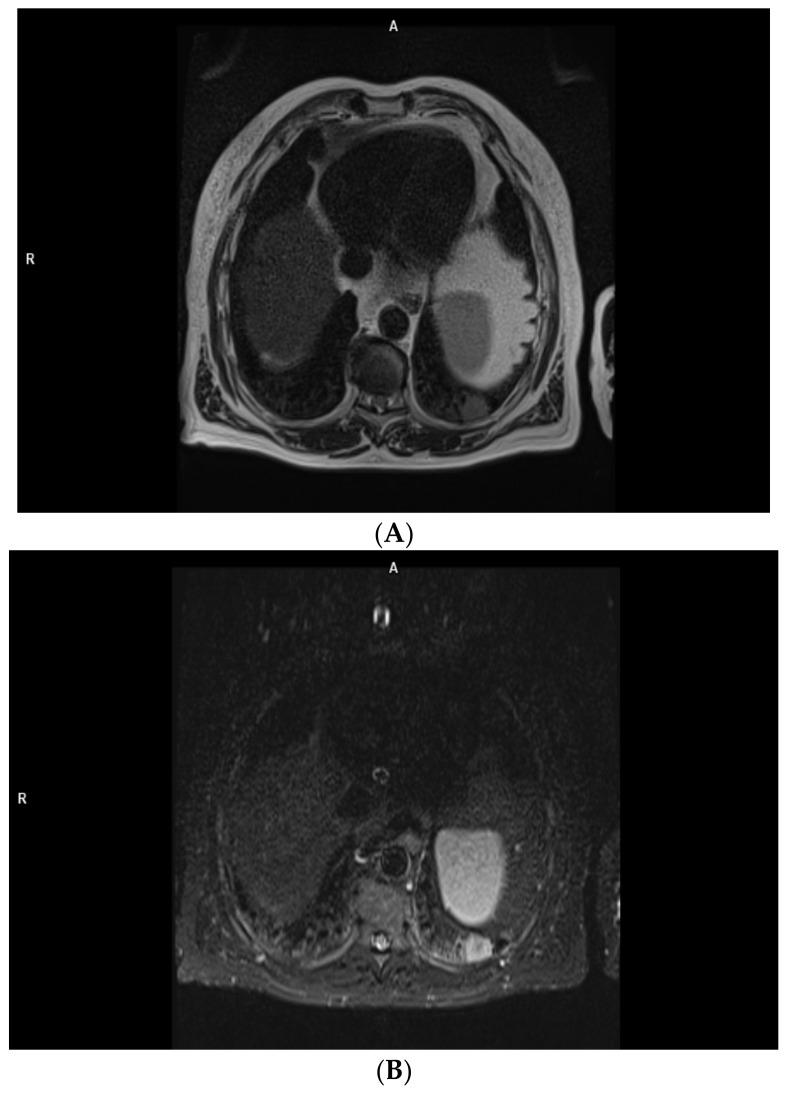

Pleural Neoplasms-What Could MRI Change?

The primary pleural neoplasms constitute around 10% of the pleural tumors. The currently recommended method for their imaging is CT which has been shown to have certain limitations. Strong development of the MRI within the last two decades has provided us with a number of sequences that could potentially be superior to CT when it comes to the pleural malignancies' detection and characterization. This literature review discusses the possible applications of the MRI as a diagnostic tool in patients with pleural neoplasms. Although selected MRI techniques have been shown to have a number of advantages over CT, further research is required in order to confirm the obtained results, broaden our knowledge on the topic, and pinpoint the sequences most optimal for pleural imaging, as well as the best methods for reading and analysis of the obtained data.